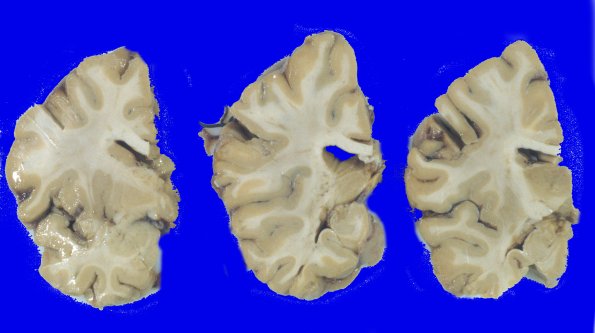

Even though her brain weight was diminished significantly, the coronal sections showed mild atrophy and minimal blunting and dilatation of the lateral ventricles.